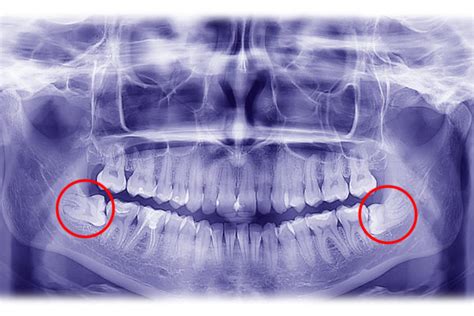

Los cordales incluidos o molares incluidos son dientes que no han erupcionado por completo y permanecen dentro del hueso. Estos dientes suelen ser los terceros molares, también conocidos como muelas del juicio.

Los cordales incluidos se dan cuando el diente que permanece totalmente dentro del hueso. Si el diente se encuentra en una posición incorrecta pero cerca de su lugar, hablamos de una inclusión ectópica, o si la pieza se encuentra en una posición incorrecta y alejada de su sitio, entonces es una inclusión heterópica.

El término “cordales incluidos” engloba también los cordales o muelas del juicio impactados, una situación que se da cuando la muela está parcialmente o totalmente no erupcionada y al mismo tiempo colocado contra un obstáculo (otro diente, el hueso, tejido blando o un tumor) que imposibilita su erupción normal.

- Impactados: Son los cordales que han intentado salir, pero están en una posición incorrecta, chocando contra otros dientes o el hueso.